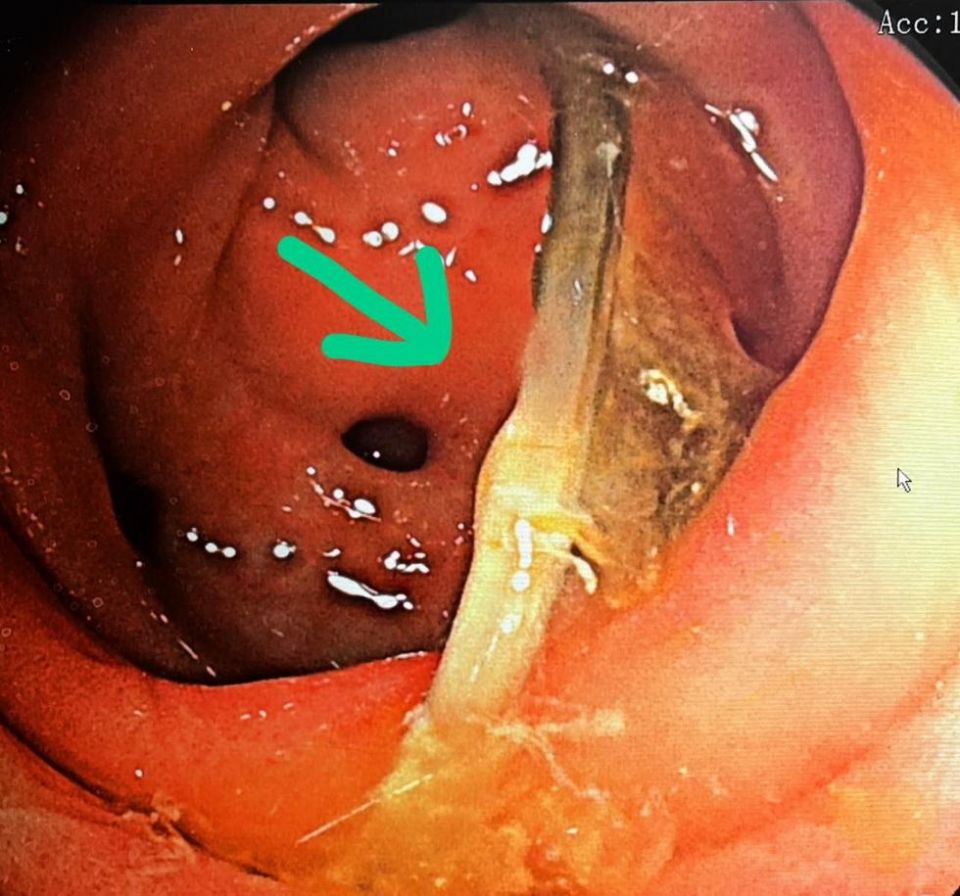

在家人建議下至天主教聖馬爾定醫院求診,肝膽腸胃科醫師羅清池建議他做大腸鏡,檢查中發現原來有一根長約四公分的魚刺,就卡在乙狀結腸,兩端就牢牢地刺在大腸壁上,醫師馬上使用專用的金屬夾,成功將魚刺夾出。取出魚刺後的隔天,腹部疼痛明顯改善,讓阿伯非常高興。

羅清池醫師表示,通常魚刺會卡在消化道的三個狹窄處,由上而下分別為賁門、幽門、及廻盲瓣,以阿伯這麼長的魚刺,居然可以「身騎白馬走三關」,一路漂流到乙狀結腸才卡住,實在少見。而且魚刺兩端就卡在腸壁上,差點就會造成腸穿孔,真的非常危險,所幸成功將它夾出,不然也有可能會造成腹膜炎或敗血症。